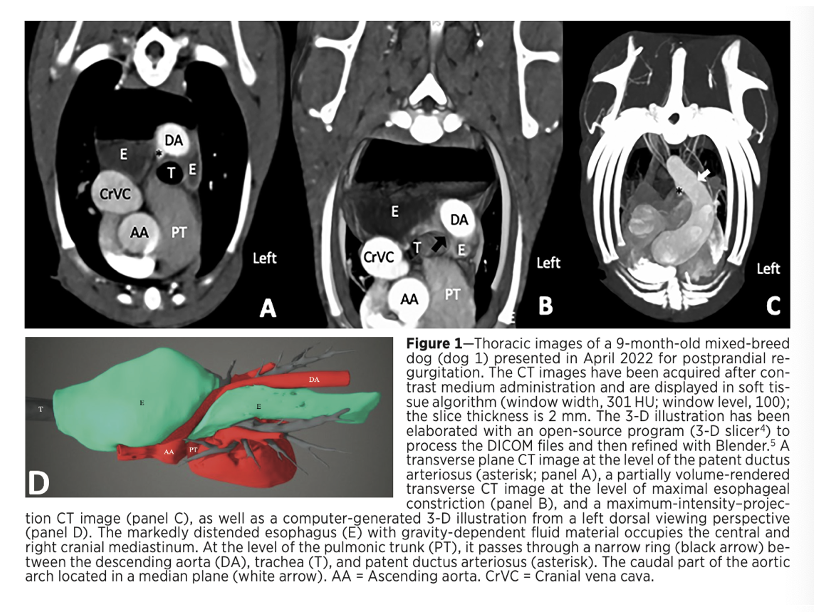

Rossie JAVMA 2024-

What new vascular ring anomaly in dogs was identified?

What were the CT findings associated with this vascular ring anomaly?

What other congenital anomalies were found with this one?

A

• Circumflex left aortic arch

• CT revealed a normal leftward oriented cranial half and an abnormal caudal half of the aortic arch crossing toward the right dorsal hemithorax leading to esophageal constriction in all dogs

• In addition, 1 dog presented with a right patent ductus arteriosus and 1 with an aberrant right subclavian artery

NOTE:

* Clinical signs include postprandial regurgitation and poor growth

* Circumflex left aortic arch vascular ring anomaly cannot be surgically corrected via the left thoracotomy that is commonly used for the more common vascular ring anomalies in dogs